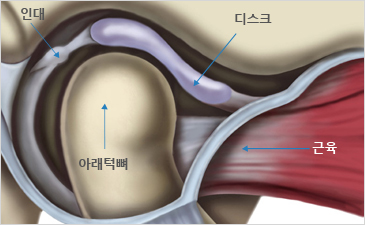

턱관절 디스크의 위치는 정상적이고, 턱뼈에도 이상이 없는

상태입니다. 턱을 열고 닫을 때 불편감을 느끼지만,

턱관절에서 소리가 나지 않고 통증도 심하지 않은

경우입니다. 대개 약 2주에서 1개월 정도의 치료로

좋아지는 경우가 많습니다.

정상디스크 위치

입을 다물고 있는 상태

입을 열고 있는 상태

정상 디스크 위치